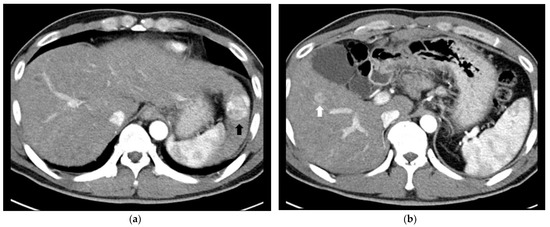

2.2. Surgical Resection plus Intraoperative Radiofrequency Ablation

- Park, H.S.; Kim, Y.J.; Yu, M.H.; Jung, S.I.; Jeon, H.J. Real-time contrast-enhanced sonographically guided biopsy or radiofrequency ablation of focal liver lesions using perflurobutane microbubbles (sonazoid): Value of Kupffer-phase imaging. J. Ultrasound Med. 2015, 34, 411–421. [Google Scholar] [CrossRef] [PubMed] [Green Version]